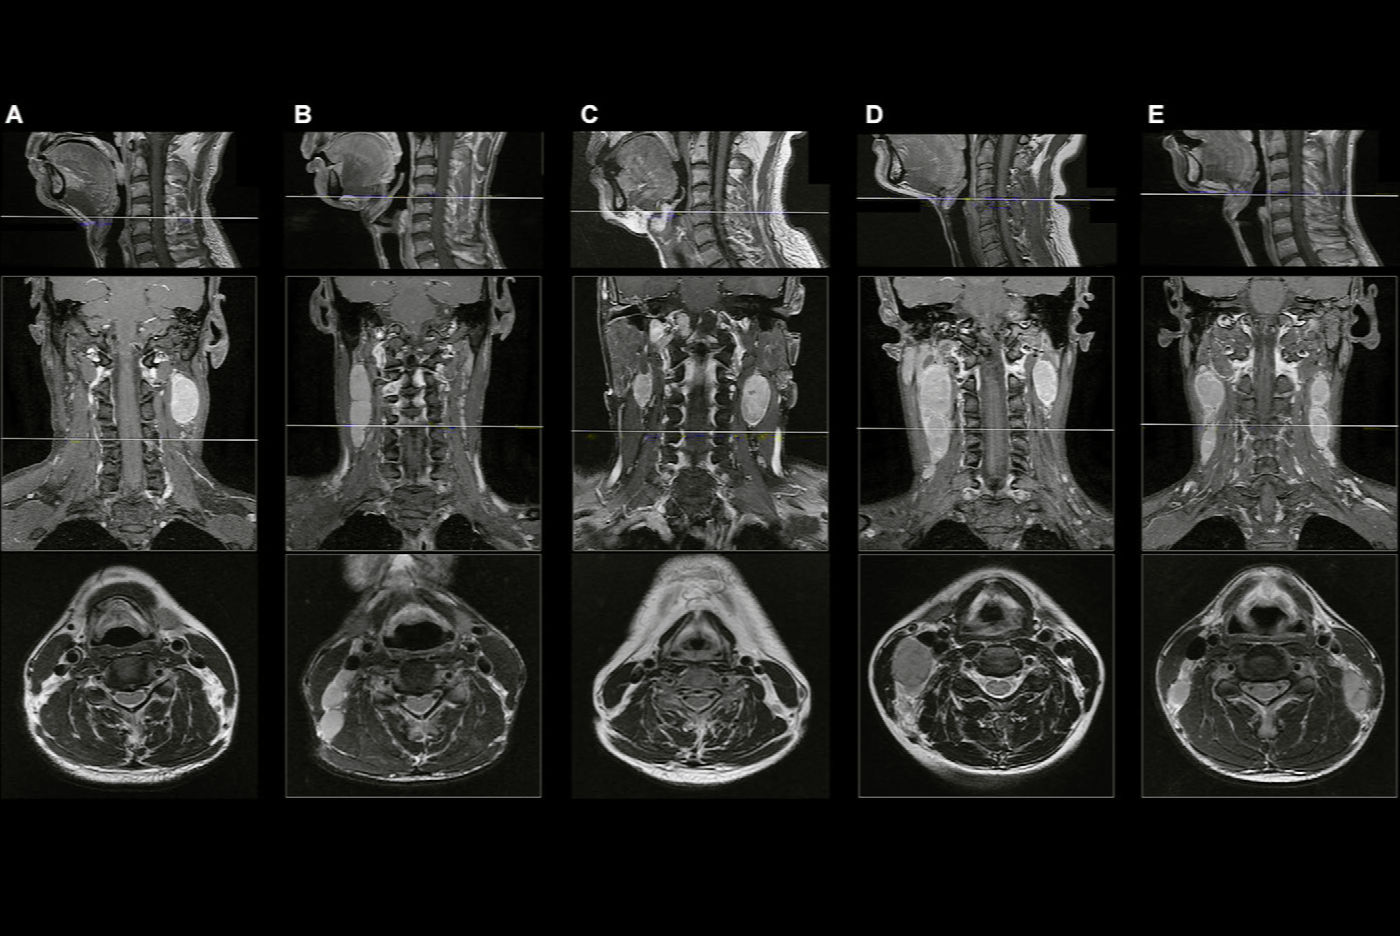

As a result, the researchers sought to develop an AI-based contouring tool to automate the contouring of primary gross tumor volume in patients with nasopharyngeal carcinoma. The researchers first gathered MRI datasets encompassing the nasopharynx from 1,021 patients with nasopharyngeal carcinoma between September 2016 and September 2017. Two experts delineated the primary gross tumor volume in consensus for all patients.

Of the 1,021 image sets, 715 were used to train a 3D convolutional neural network, and 103 were utilized for validation. In testing on the remaining 203 cases, the algorithm yielded a Dice similarity coefficient (DSC) of 0.79 and a 2-mm average surface difference in comparison with the ground truth contours.

In a multicenter study, the researchers then compared the performance of the AI algorithm with eight radiation oncologists on a random sample of 20 test MRI exams.